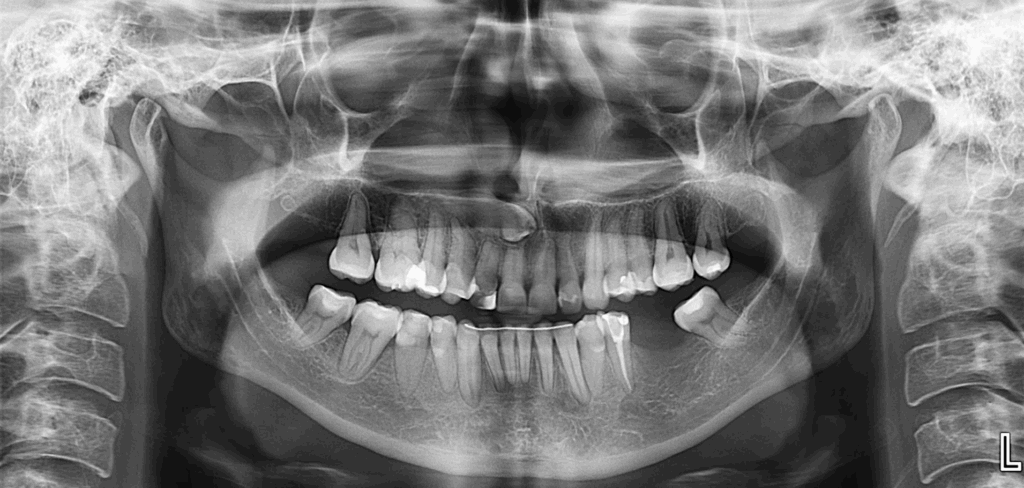

En la radiografía panorámica (Figura 1), se aprecia pieza 13 en posición ectópica y además se observa imagen radiolúcida proyectados en tercio apical de pieza 33.

Radiografia Panorámica